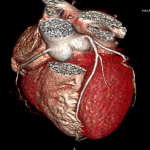

女性,43歲,心跳速率每分鐘56下,BMI: 20 顯影劑速率4.0ml/s 總量 67ml/輻射劑量1.9mSv